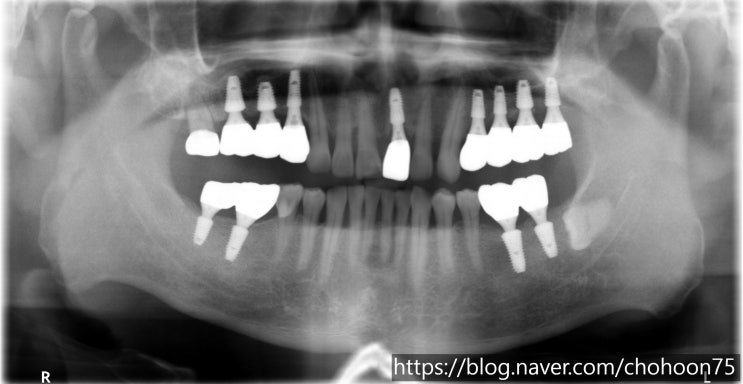

[조훈치과] 싱글 임플란트 치료 증례

안녕하세요. 조훈 치과입니다. 싱글 임플란트 (Single Implant)는 가장 흔한 임플란트 유형으로, 개별적...